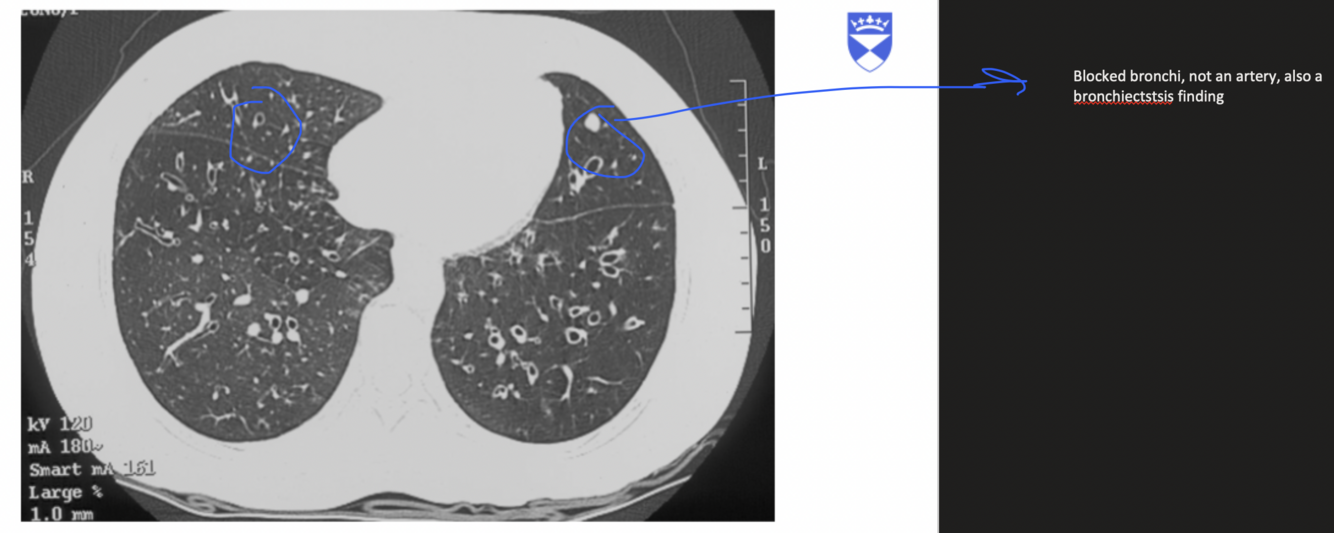

What is tree-in bud opacification ?

Suggestive of bronchiecstasis

-Suggesting small airway mucus impaction

-Small, branching, nodular structures in the lungs that resemble a budding tree

Seen in CT

What is signet-ring sign ?

In lungs bronchi travel with an artery which should be larger; in bronchiecstasis, the bronchi are larger

-white is artery black is borochi